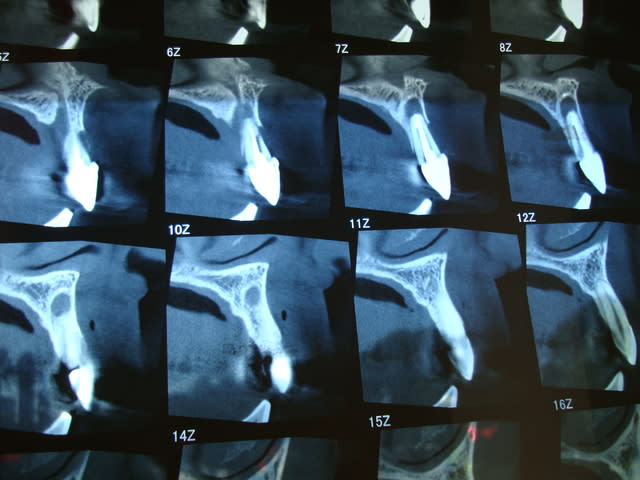

SCAN

Il y a 3.6 mm d'os au dessus du granulome